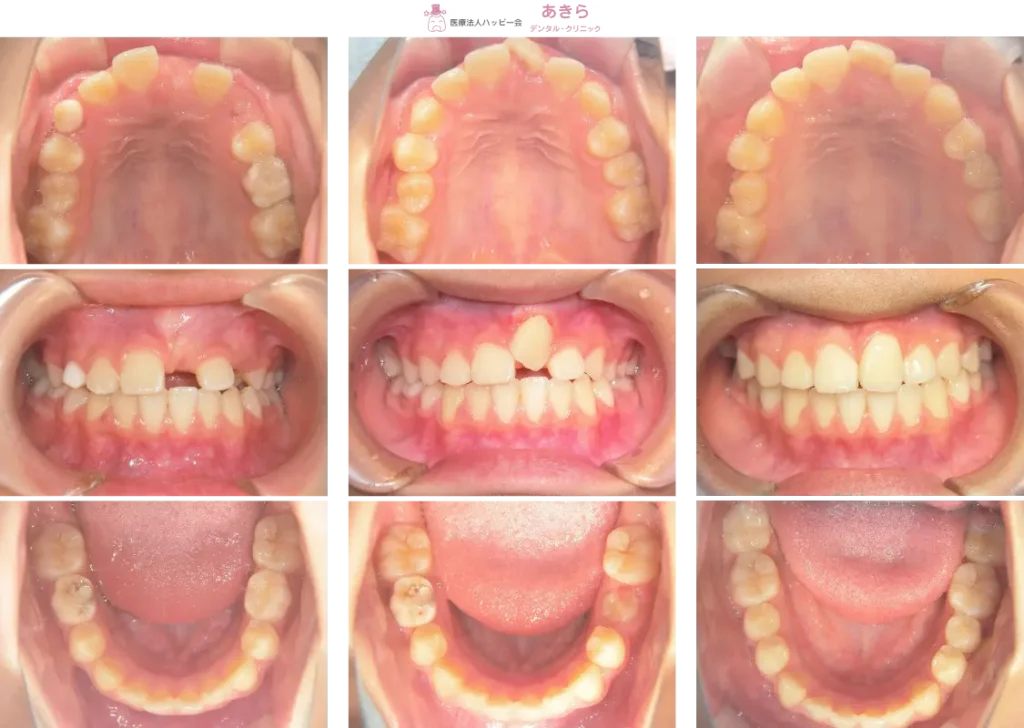

SH療法-症例-No.009-前歯の萌出遅延と埋伏を伴う難症例

山形市の歯医者「あきらデンタル・クリニック」のSH療法の症例をご紹介します。 SH… -

予防的矯正治療(プレオルソやマウスピース型装置を主に使用)-症例-No.005

山形市の歯医者「あきらデンタル・クリニック」の予防的矯正治療(プレオルソやマ… -

SH療法-症例-No.008-上顎左右5番の萌出障害を伴うケース

症例

予防的矯正治療(プレオルソやマウスピース型装置を主に使用)-症例-No.004

SH療法-症例-No.007-前歯の捻じれと叢生(凸凹)を伴うケース

予防的矯正治療(プレオルソやマウスピース型装置を主に使用)-症例-No.003